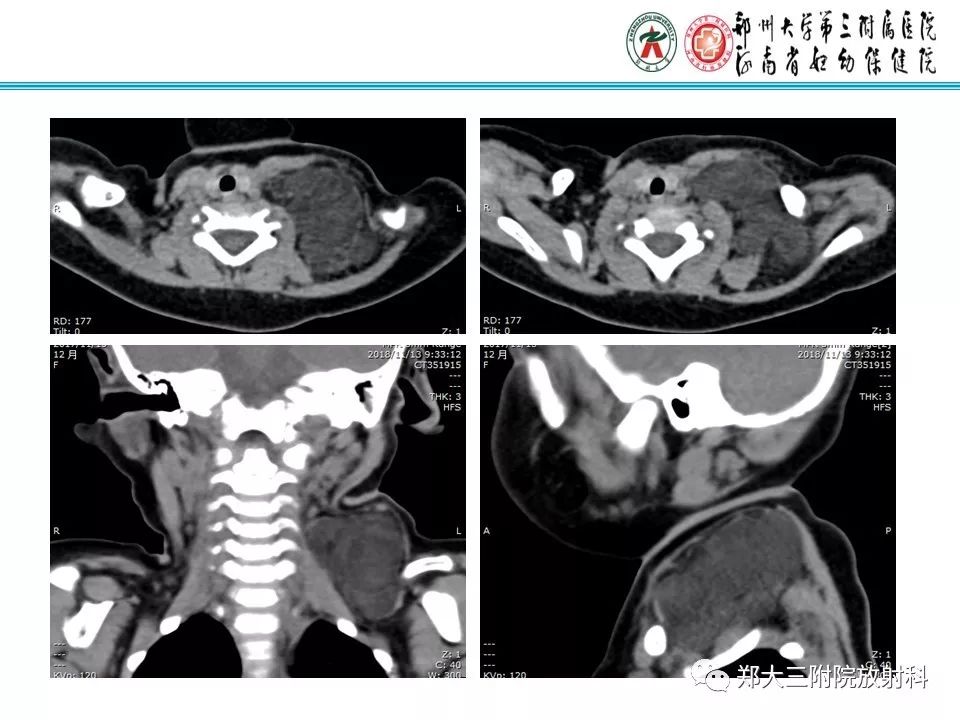

儿童颈部脂肪母细胞瘤1例CT影像诊断

【病例】儿童颈部脂肪母细胞瘤影像诊断